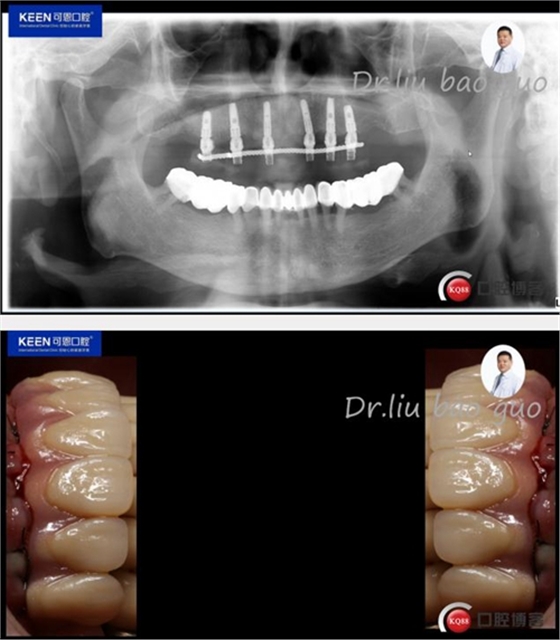

義齒試戴及戴入后照片